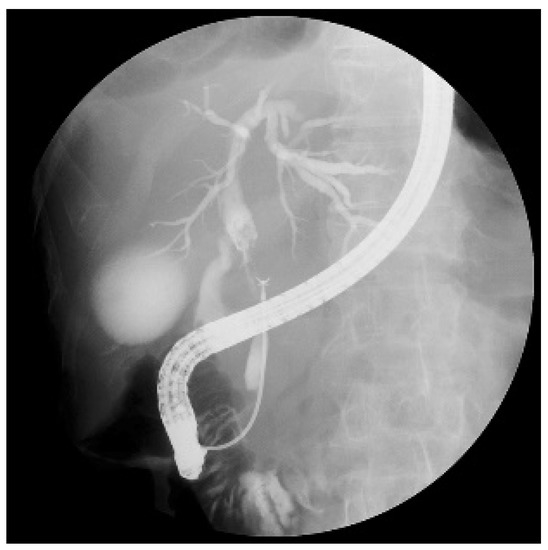

2.4. Endoscopic Procedures